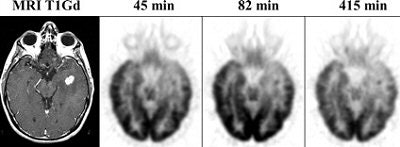

![]() |

| A 38-year-old man with a recurrent left temporal astrocytoma. Coregistration of T1Gd MRI planes with the F-18 FDG PET planes and use of delayed imaging made evident that the small focus seen on MRI was a tumor rather than radionecrosis, especially at 415 min. Subsequent MRI confirmed rapidly progressing disease. Reprinted by permission of the Society of Nuclear Medicine from Spence AM, Muzi M, Mankoff DA, et al, "18-FDG PET of Gliomas at Delayed Intervals; Improved Distinction Between Tumor and Normal Gray Matter" (J Nucl Med 2004; 45: 1653-1659, p. 1655 [Figure 3]). |